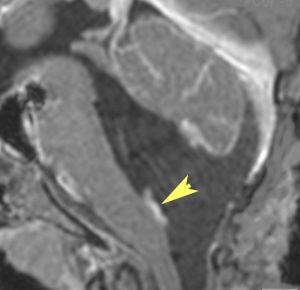

中脳視蓋毛様細胞性星細胞腫 tectal glioma(詳しくはここをクリック)

中脳視蓋グリオーマとして知られるものです。この腫瘍は基本的には,初回手術で全摘出できるのですが,現実的には,技術的に難しすぎるので部分摘出で終えることが多いでしょう。この子は,15歳の時に閉塞性水頭症のために,頭痛,嘔吐,意識障害,瞳孔不同となりました。開頭部分摘出術と第3脳室開窓術で回復して,その後にカルボプラチンとビンクリスチンの化学療法を受けました。でも腫瘍増大が止められずに,発症1年後に54グレイ30分割の放射線治療を受けています。さらにその半年後くらいから再増大しましたが,スードプログレッションと考えられました。のう胞性拡大が止まらず,発症3年後にまた再開頭手術で亜全摘出しました。